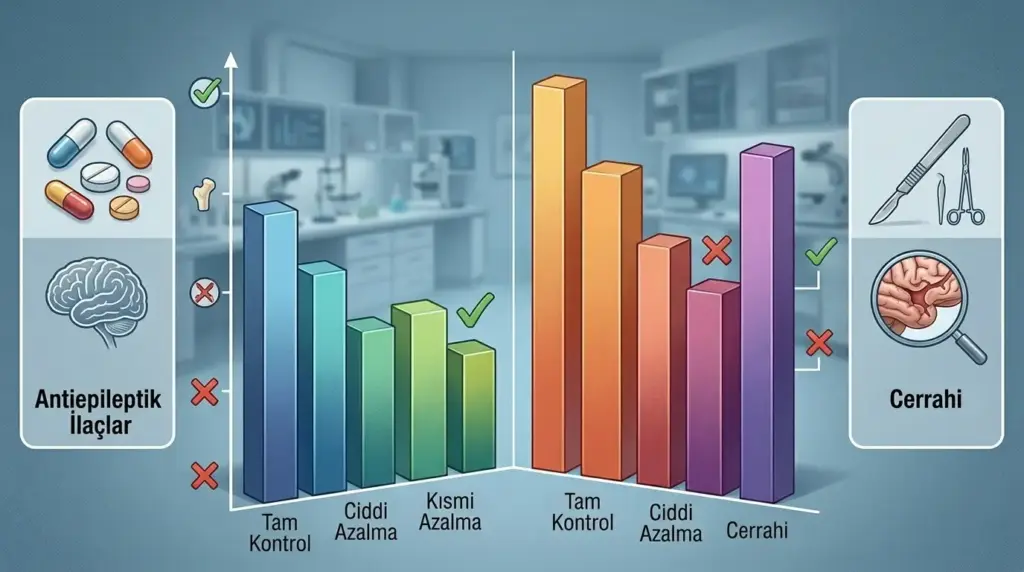

● İlaç tedavisi (antiepileptikler) nöbetleri geçici olarak baskılayabilir; ancak kavernomun kendisini ortadan kaldırmaz ve hastaların önemli bir bölümünde uzun vadede yetersiz kalır.

● Cerrahi, özellikle ilaçlara dirençli nöbetlerde birinci tercih tedavi yöntemidir; 45 çalışmayı kapsayan bir meta-analizde cerrahi uygulanan hastalarda nöbet kontrol oranı yüzde 79 olarak bildirilmiştir.

Bir çalışmada, yalnızca ilaçla izlenen hastalarda tedavi sonunda 2 yıl nöbetsiz kalma oranı yüzde 32 iken erken cerrahi uygulanan hastalarda bu oran yüzde 88 olarak saptanmıştır (PubMed, Journal of Neurosurgery). Benzer şekilde, ilaç grubunda hastaların yalnızca yüzde 8’i antiepileptik ilaçlarını tamamen bırakabilirken, cerrahiden sonra bu oran yüzde 78’e yükselmiştir.

Kavernom Nöbetinde Cerrahi Tedavi: Kimler Aday?

Mikrocerrahi rezeksiyon, kavernomla ilişkili epilepside tedavinin altın standardı olarak kabul görmektedir. 45 çalışmayı kapsayan bir sistematik derleme ve meta-analizde cerrahi uygulanan hastalarda nöbet kontrol oranı yüzde 79 (yüzde 95 güven aralığı: 75–83) bulunmuştur (PMC/Frontiers, 2020). Aynı analizde radyocerrahi uygulanan grupta bu oran yüzde 49 (yüzde 95 GA: 38–59) olarak bildirilmiştir.

| Karşılaştırma Kriteri | İlaç Tedavisi | Mikrocerrahi |

|---|---|---|

| 2 yıl nöbetsiz kalma oranı | ~%32 | ~%88 |

| İlaca bağımlılıktan kurtulma | ~%8 | ~%78 |

| Kavernomu ortadan kaldırır mı? | Hayır | Evet |

| Kanama riskini yok eder mi? | Hayır | Evet (tam çıkarımda) |

| Uygulama riski | Düşük | %3–4,4 kalıcı morbidite |